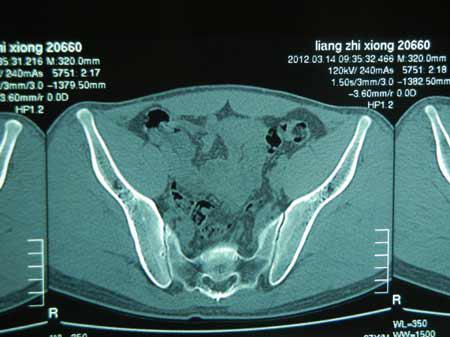

骨盆正位片示:双侧髋关节间隙明显变窄,关节面欠光滑,双股骨头骨纹理欠规则,双侧骶髂关节间隙消失,所示腰椎呈竹节样改变,双侧耻骨联合骨质欠清晰,右股骨颈结构欠规则;腰背部及多关节僵硬、疼痛,活动受限;双侧髋关节、骶髂关节破坏。

蒙兴文主任分析:强直性脊柱炎骶髂关节疼痛特点是休息不能缓解,活动后方能缓解,这也是与腰椎间盘突出、腰椎管狭窄、腰部外伤的区别点。董先生属于强直性脊柱炎稍微严重者,不仅会感觉骶髂关节部僵硬、肌肉酸痛,而且腰背部及多关节僵硬、疼痛,活动受限;白细胞轻度减少,血沉、C反应蛋白偏高;颈椎曲度变直;双侧髋关节、骶髂关节破坏。原因是肌腱、韧带与骶髂关节的骨附着点炎症,即肌腱末端炎,易误诊。

(图:董先生入院检查所拍摄的CT影像图)